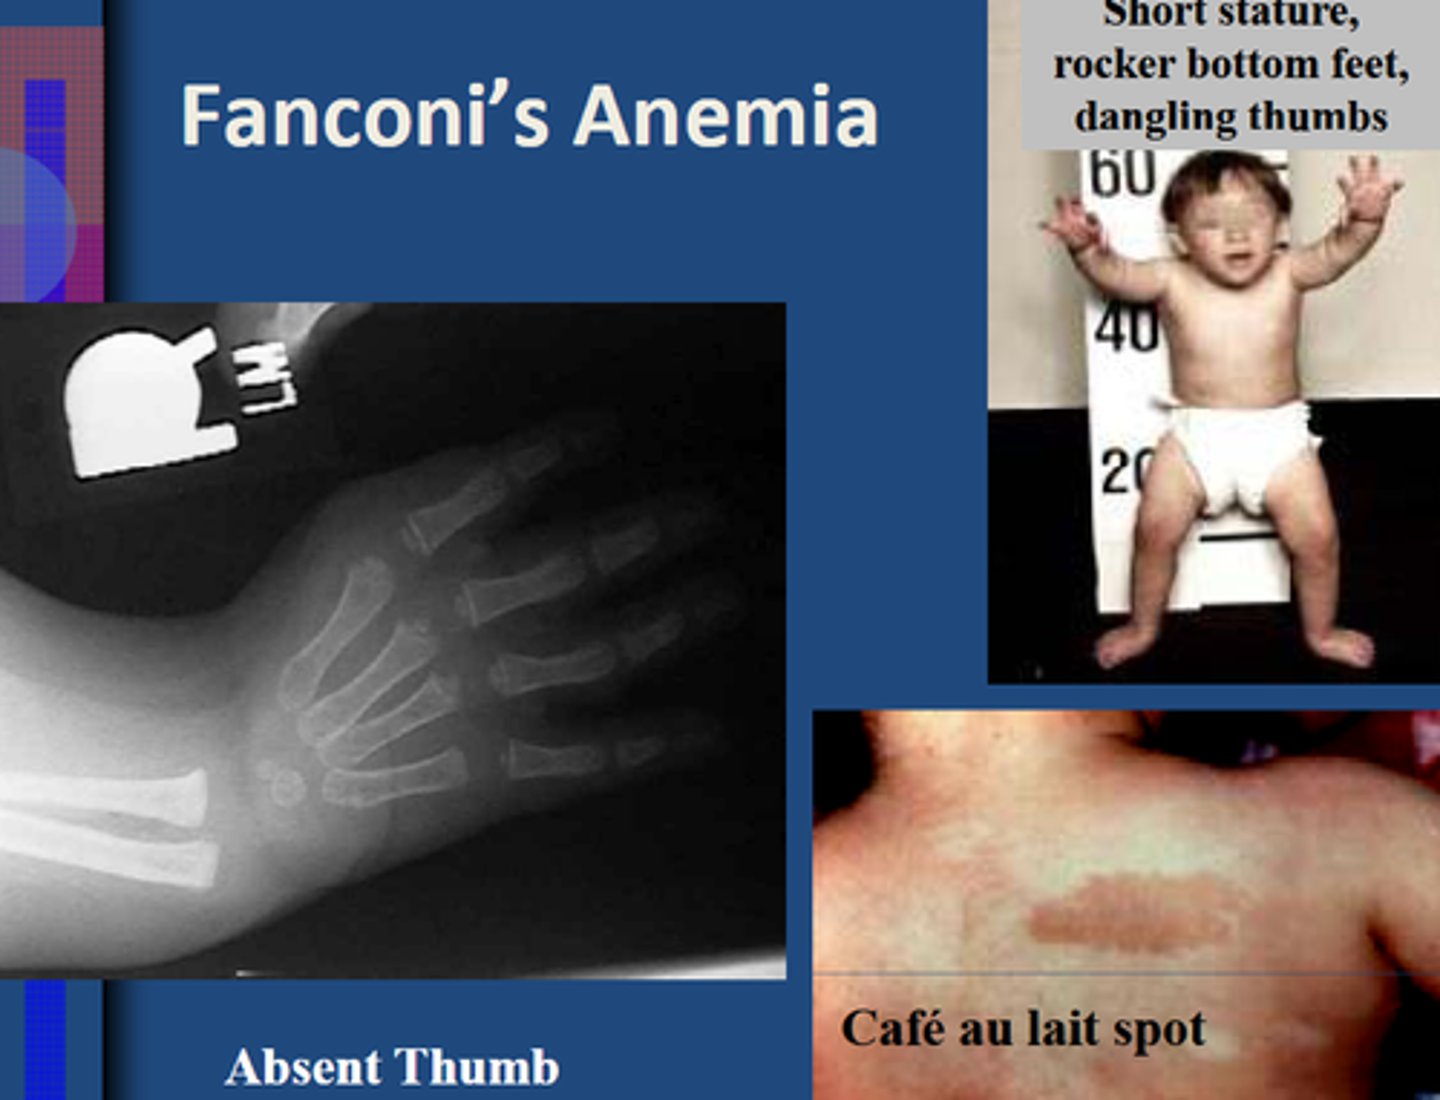

Short stature, cafe au lait spots, thumb/radial defects, increased incidence of tumors/leukemia, aplastic anemia

Fanconi anemia (genetic loss of DNA crosslink repair; often progresses to AML)